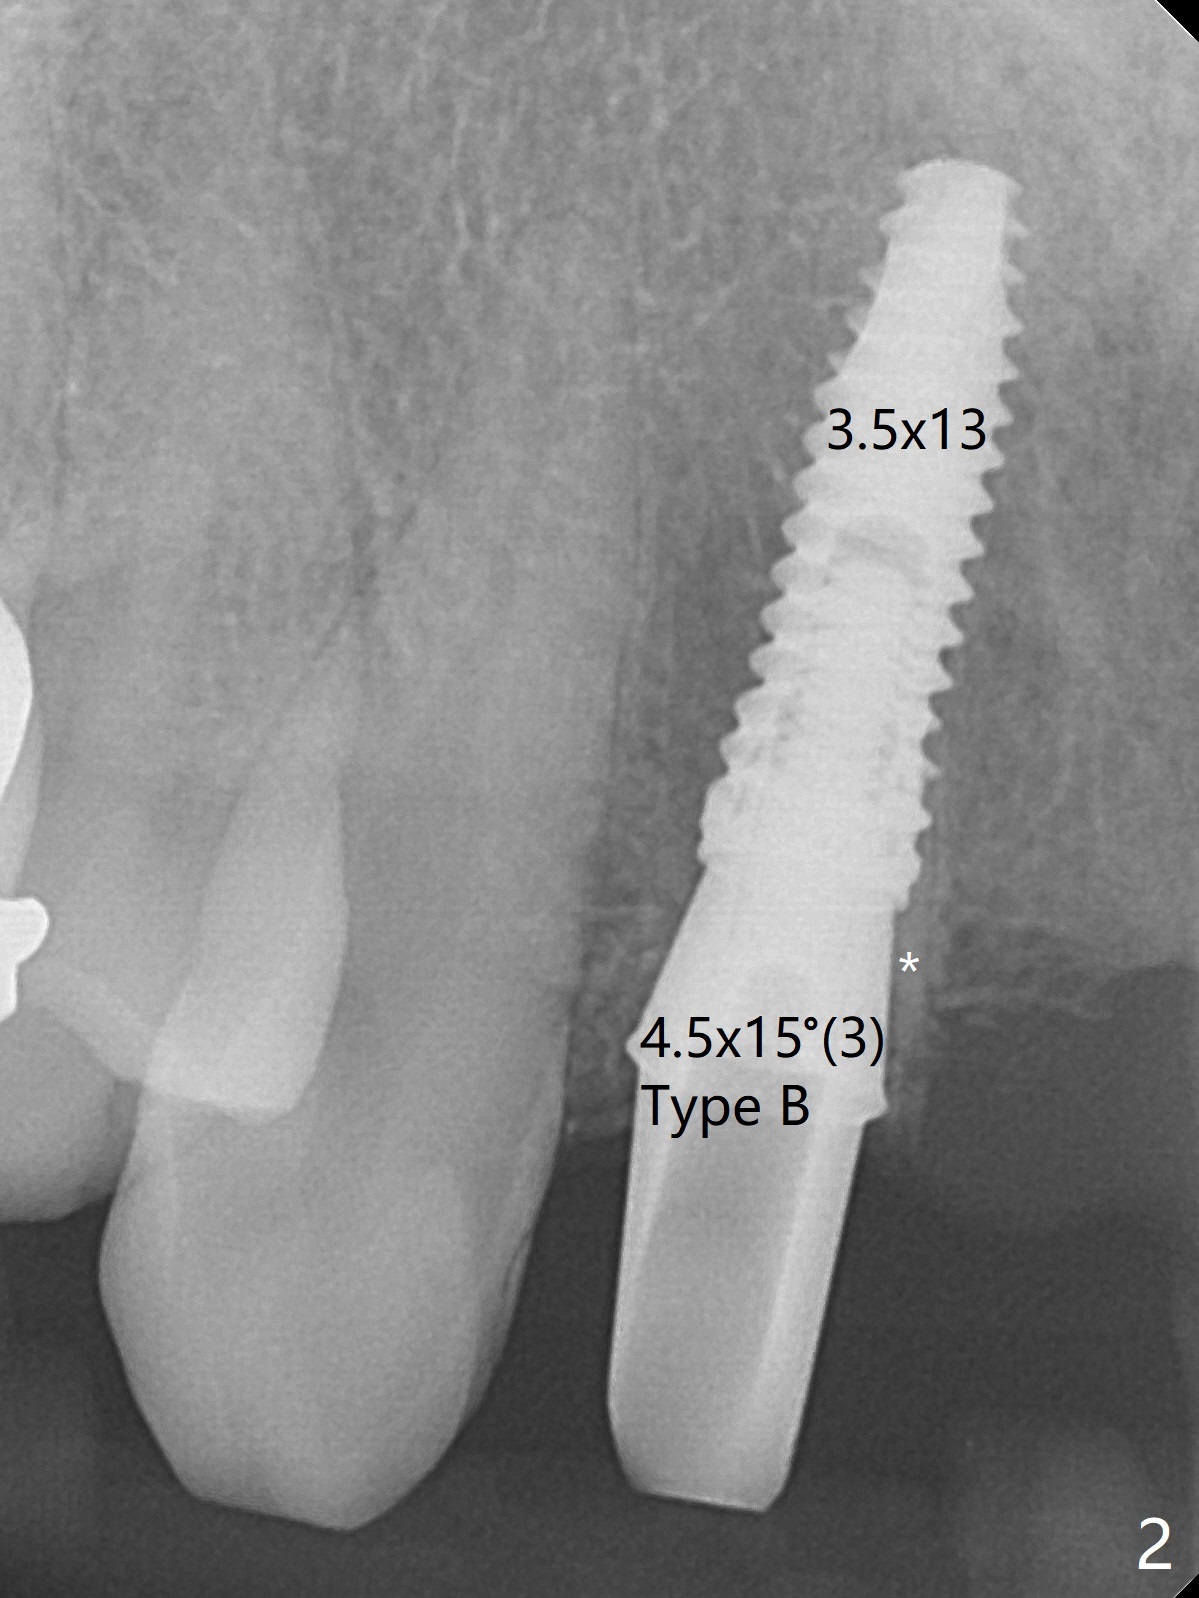

Since the pontic (Fig.1 #8) of the existing failed FPD has severe buccal concavity (*), socket shield is performed when #7 and 9 are extracted (Fig.2,3 *). Angled abutments are placed when 3.5x13 mm implants are inserted with guide. An immediate provisional FPD is fabricated. Acrylic is added to the pontic of the temporary FPD (Fig.4 arrow) to form a concave pontic gingiva (blanch)16 days postop. The patient returns 3.5 m postop with concern over temp being bulky and turning yellow. With Cetacaine and 1-0 cord, labial reducion is done for 7,9 abutments as well as 7 incisal reduction. The provisional is relined to increase 7 8 crown length. Next visit we will continue modification of temporary. Photos will be taken before and after modification (buccal and incisal views). The patient complains of occasional pain at #7. Check whether the socket shield at #7 is a culprit. In fact the implant at #7 is normal. Manipulation of the provisional does not help cosmetics much. A permanent restoration is delivered 5.5 months postop (Fig.7-9).